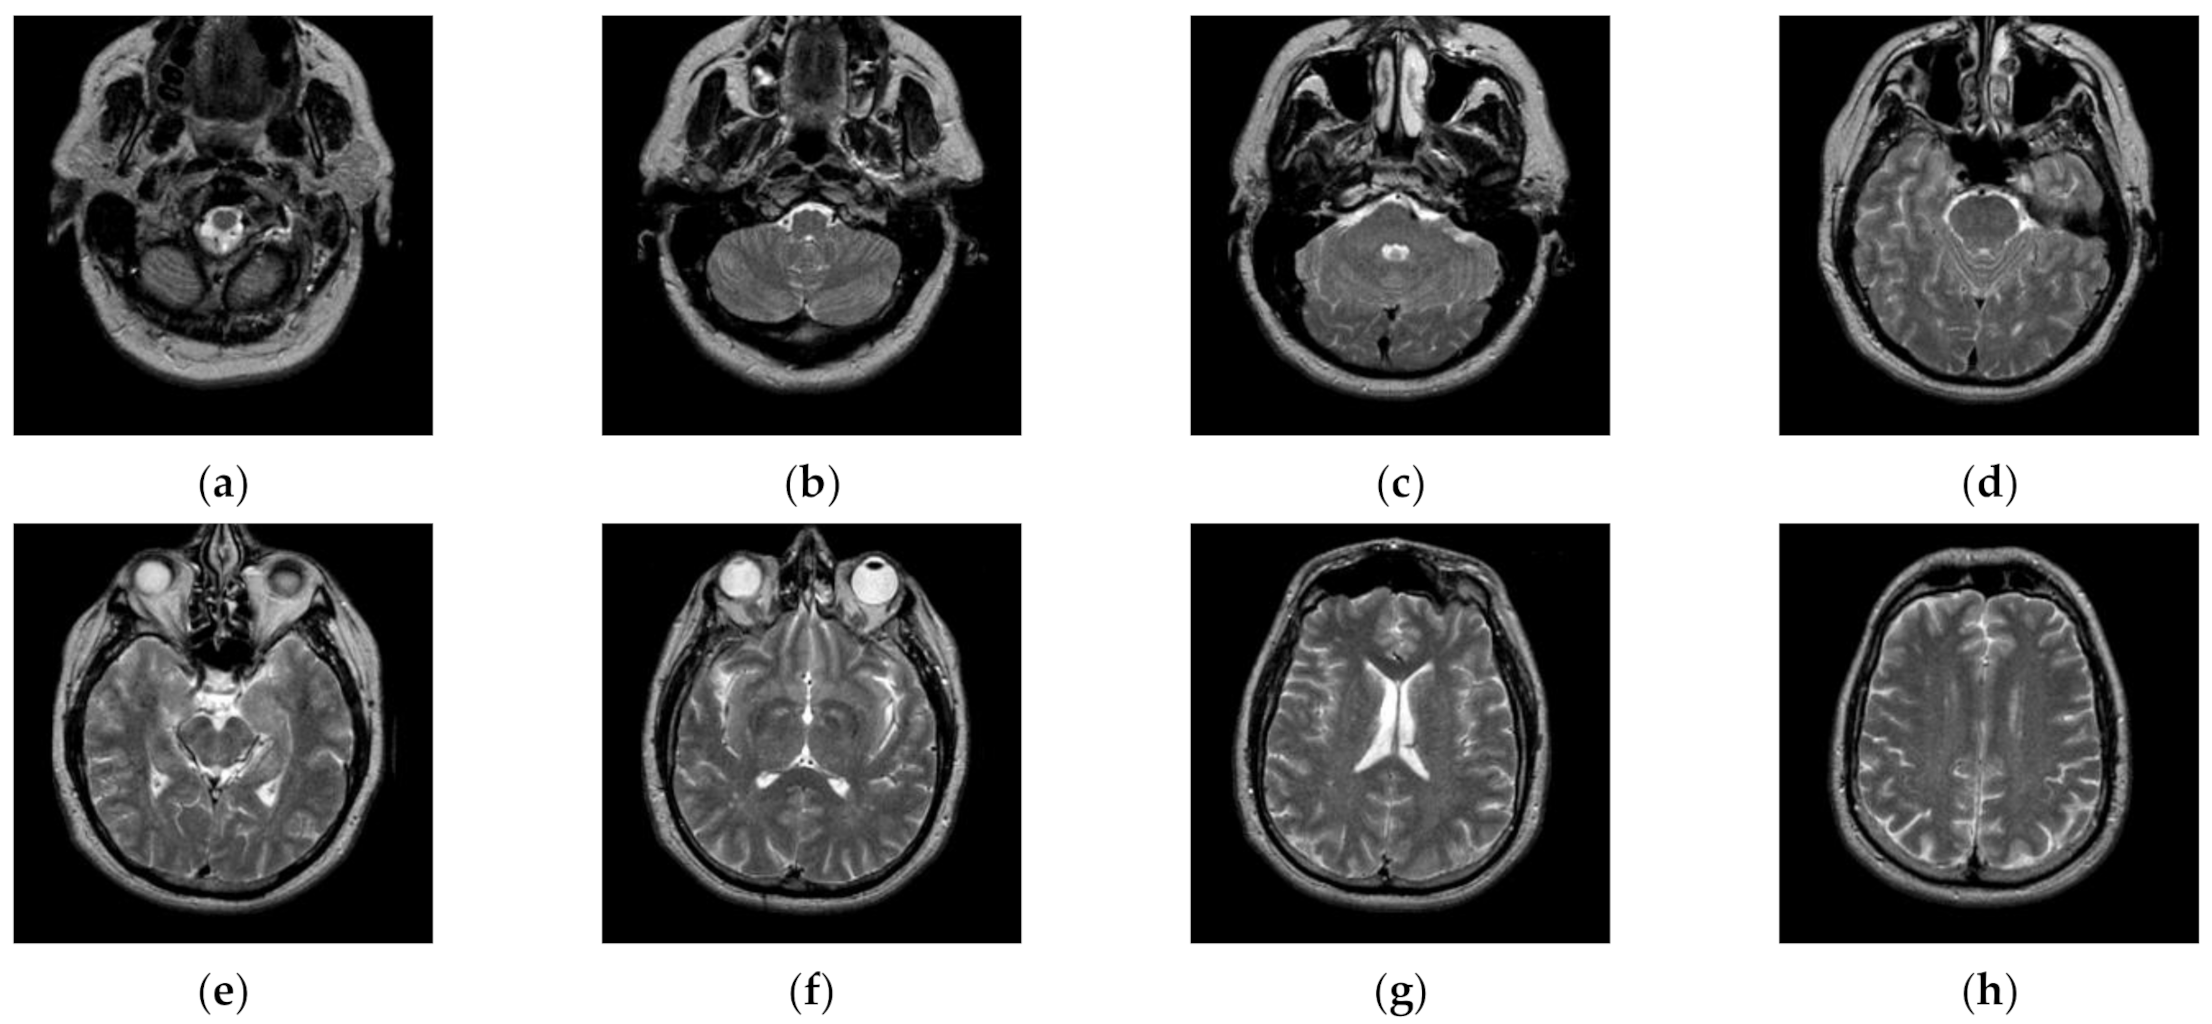

Transaxial MR-T2 brain images with various slices downloaded from “The Whole Brain Atlas” of Harvard Medical School (http://www.med.harvard.edu/aanlib/home.html, accessed on 17 May 2021) were used in the segmentation experiments. Because space is limited, the ten brain slices #022~#112 displayed in Figure 9 were chosen to demonstrate the performance of our proposed algorithm. Parameters for the proposed algorithm are listed in Table 1. All experiments were performed on a computer with Intel(R) Core(TM) i7-7500U CPU, 2.70 GHz, 8GB RAM, Windows 10 using MATLAB 8.1.0.604 (R2013a).

Figure 9.

MR-T2 brain slices: (a) slice #022, (b) slice #032, (c) slice #042, (d) slice #052, (e) slice #062, (f) slice #072, (g) slice #082, (h) slice #092, (i) slice #102, (j) slice #112.